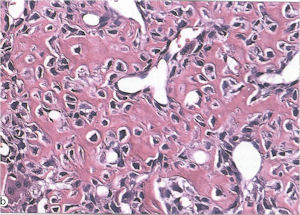

Aggressive Osteoblastoma

- Aggressive osteoblastoma is a distinct rare type of osteoblastoma that has a much more aggressive local behavior than a conventional osteoblastoma. They have a higher chance for local recurrence after removal.

- There has been controversy about the true existence of this type of tumor and whether these tumors are actually low grade osteosarcomas.

- They have a similar appearance microscopically as a conventional osteoblastoma except the osteoblasts are twice as large and have an epithelioid quality with abundant eosinophilic cytoplasm (Epithelioid Osteoblasts).

- Aggressive osteoblastoma is a borderline lesion lesion between osteoblastoma and osteosarcoma. It is not a precursor to osteosarcoma. It does not metastasize.

- Aggressive osteoblastomas usually occur in an older age group than conventional osteoblastoma.

- Most patients are older than age 30. It affects a broad variety of bones.

- Aggressive osteoblastomas are usually larger than a conventional osteoblastoma and have been reported to be up to 8.5 cm in diameter.

- Most have a similar radiographic appearance as a conventional osteoblastoma and have well defined margins, variable amounts of mineralization and peritumoral sclerosis. They occasionally have radiographic characteristics consistent with malignancy.

- Aggressive osteoblastomas are locally aggressive but never metastasize.